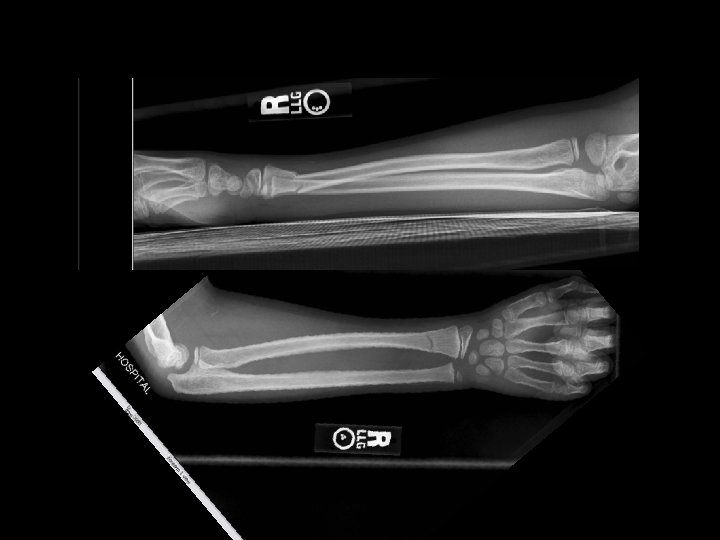

Go to: Immob_Early_Motion_Guides. html to see details of each - Type of Fracture, Dislocation, Ligament Rupture Immobilization/Early Motion Timelines Common Complications (Secondary Problems) Colle’s Fx Immobilized 6 -8 weeks; AROM as each cast is removed; elevation of the hand finger flexion and extension should begin immediately as tolerated to decrease edema and guard against CRPS; OA in joints involved in fx; reduced ROM in pro/supination, elbow flexion/ext; all shoulder motions

Go to: Immob_Early_Motion_Guides. html to see details of each - Type of Fracture, Immobilization/Early Dislocation, Motion Timelines Ligament Rupture Common Complications (Secondary Problems) Proximal and Middle Phalanx Fractures If poor positioning in splint = PIP flexion contracture, MCP extension contx; In prox phal fx = adhesion of flexor tendons to fracture site; If positioned well in "clam -digger" = intrinsic + hand IF internal fixation, begin AROM and AAROM 5 to 15 days; IF 3 to 5 weeks in "clamdigger" follow by PROM to stretch intrinsics and PIP/DIP active f/e with prox phal supported in MCP extension – see OH

Go to: Immob_Early_Motion_Guides. html to see details of each - Type of Fracture, Immobilization/Early Dislocation, Motion Timelines Ligament Rupture Common Complications (Secondary Problems) Metacarpal Fractures If not positioned correctly = MCP extension contx, PIP flexion contx; Intrinsic contracture (from direct trauma and scaring in intrinsics); Decreased web space in 1 st metacarpal fx. Immobilization in "clam -digger" position 2 to 3 weeks then AROM and mild AAROM and continue splint for protection another 2 weeks; 1 st metacarpal fx splinted in thumb abduction